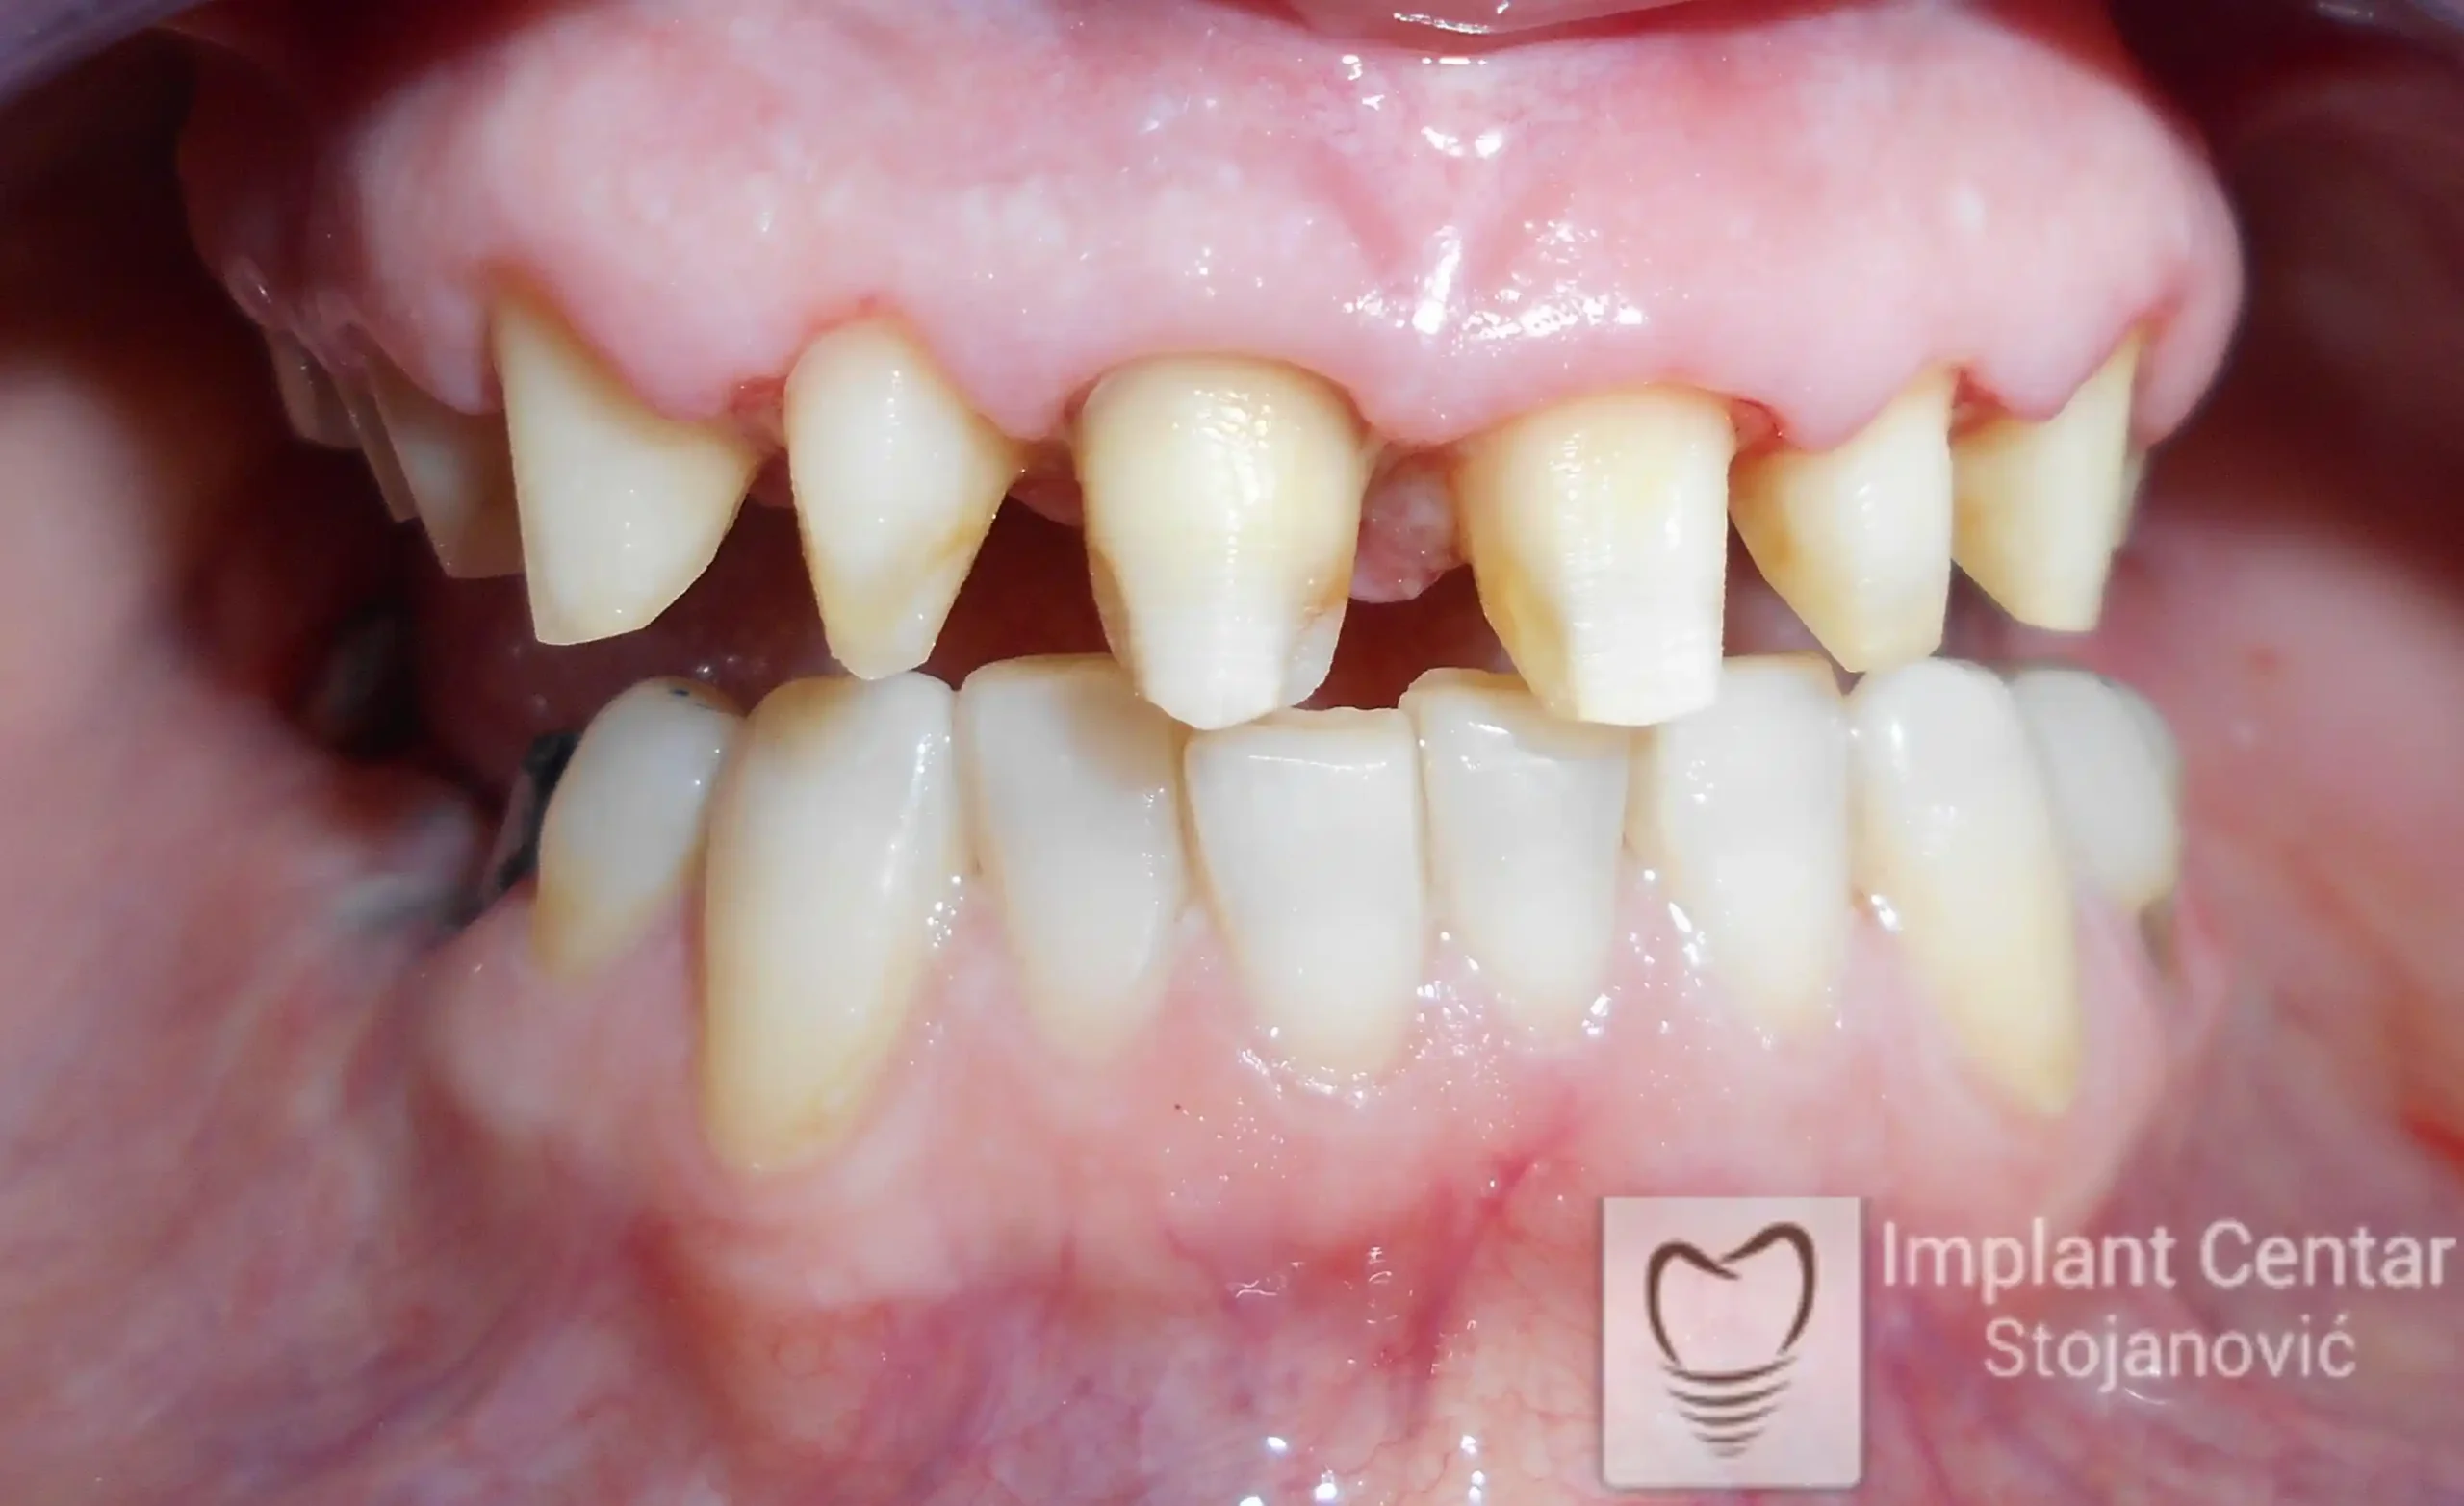

Pacijent sa rascepom usne, nepca i alveolarnog grebena uspešno je rehabilitovan fiksnim protetskim radom na implantatima. Pre dolaska u našu ordinaciju, pacijent je u gornjoj vilici nosio totalnu protezu preko preostalih zuba, dok je u donjoj vilici bio zbrinut parcijalnom mobilnom protezom. Tokom višegodišnje potrage za adekvatnim rešenjem, pacijent nije uspeo da pronađe zadovoljavajuću terapijsku opciju ni u zemlji ni u inostranstvu.

Nakon detaljnog kliničkog pregleda i analize radioloških snimaka, izrađen je sveobuhvatan plan terapije sa ciljem uklanjanja mobilnih proteza i postizanja maksimalne funkcionalne i estetske rehabilitacije. Zbog loše biološke vrednosti preostalih zuba, doneta je odluka o njihovom vađenju i ugradnji dentalnih implantata.

Na slikama 1, 2, 3 , 4  i  5 prikazan je izgled pacijenta pre početka terapije. Nakon detaljne kliničke i radiološke analize, doneta je odluka o vađenju zuba loše biološke vrednosti, dok su bezuba polja sanirana ugradnjom dentalnih implantata.